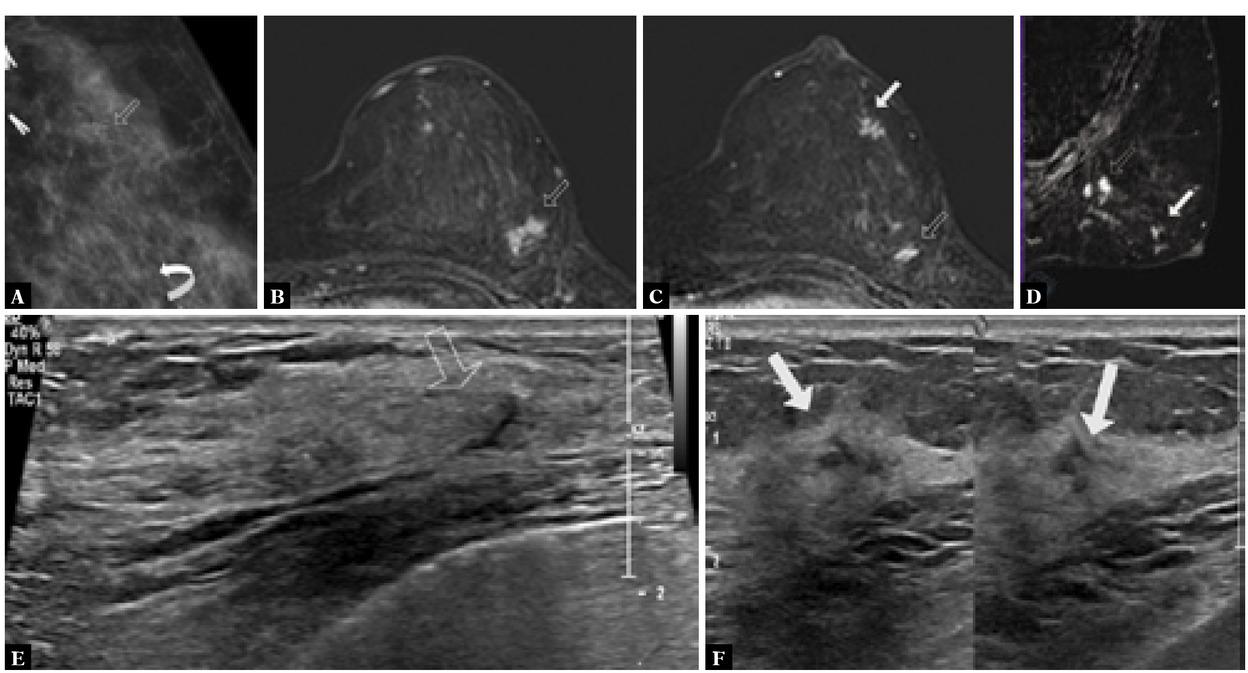

Fig. 1

A. Mammogram LMCC shows surgical clips at the surgical scar in the upper outer left breast. Group of suspicious calcifications anterior to surgical clips (arrow). Multiple other groups of suspicious linear calcifications in the lower inner left breast (curved arrow). B. Breast MRI axial subtraction post-contrast image shows a suspicious enhancing mass measuring 1.4 x 0.9 cm at the scar posteriorly. Another adjacent tiny enhancing mass seen inferiorly in the posterior third of the mid-outer left breast (image C). C. Focal non-mass enhancement at 3:00 in the anterior third of the left breast (solid arrow). D. Sagittal MR MIP rotated image shows enhancing masses at the region of the scar posteriorly (arrow) and non-mass enhancement (solid arrow). E. Ultrasound showed post-operative scar in the upper outer left breast. Subtle hypoechoic lesion anterior to the scar may correlate with suspicious calcifications on mammogram (arrow). F. Heterogeneous non-specific lesion may represent ductal abnormality in the mid-outer periareolar left breast correlating with non-mass enhancement on MRI (solid arrow)